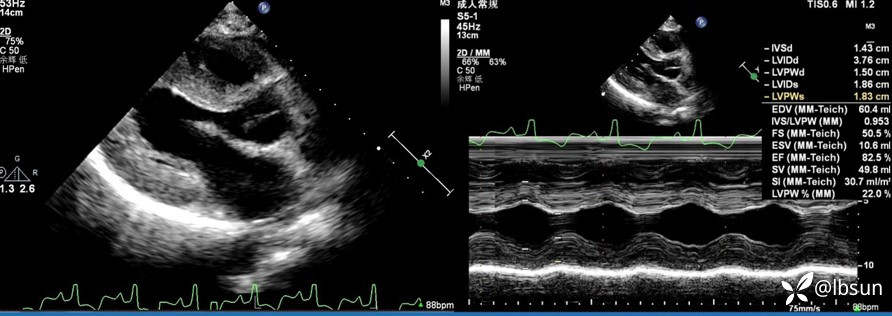

•心脏超声:左房左室内径正常,左室壁显著增厚,室壁运动正常。

补充我院的心脏超声图像